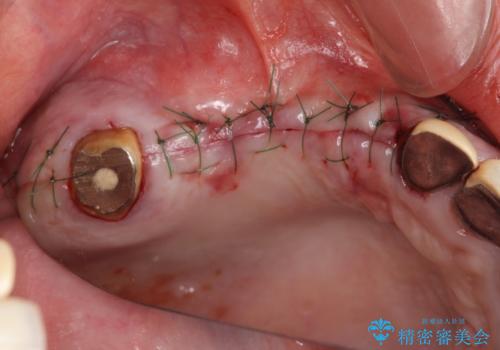

- 他院で1本インプラントを入れたまま治療に通うことができなくなり、途中からの治療を希望され来院されました。

既に埋入されているインプラントは位置が悪いのでそのまま骨内に留置することとし、新たに咬合機能を回復すべく3本のインプラントを埋入すると同時に吸収した骨幅を増やし、安定してインプラントで噛める環境整備を目指します。

インプラントが長持ちするために、インプラント周囲の十分な骨量・角化歯肉の存在・安定した咬合を一つづつ整備する治療を行いました。